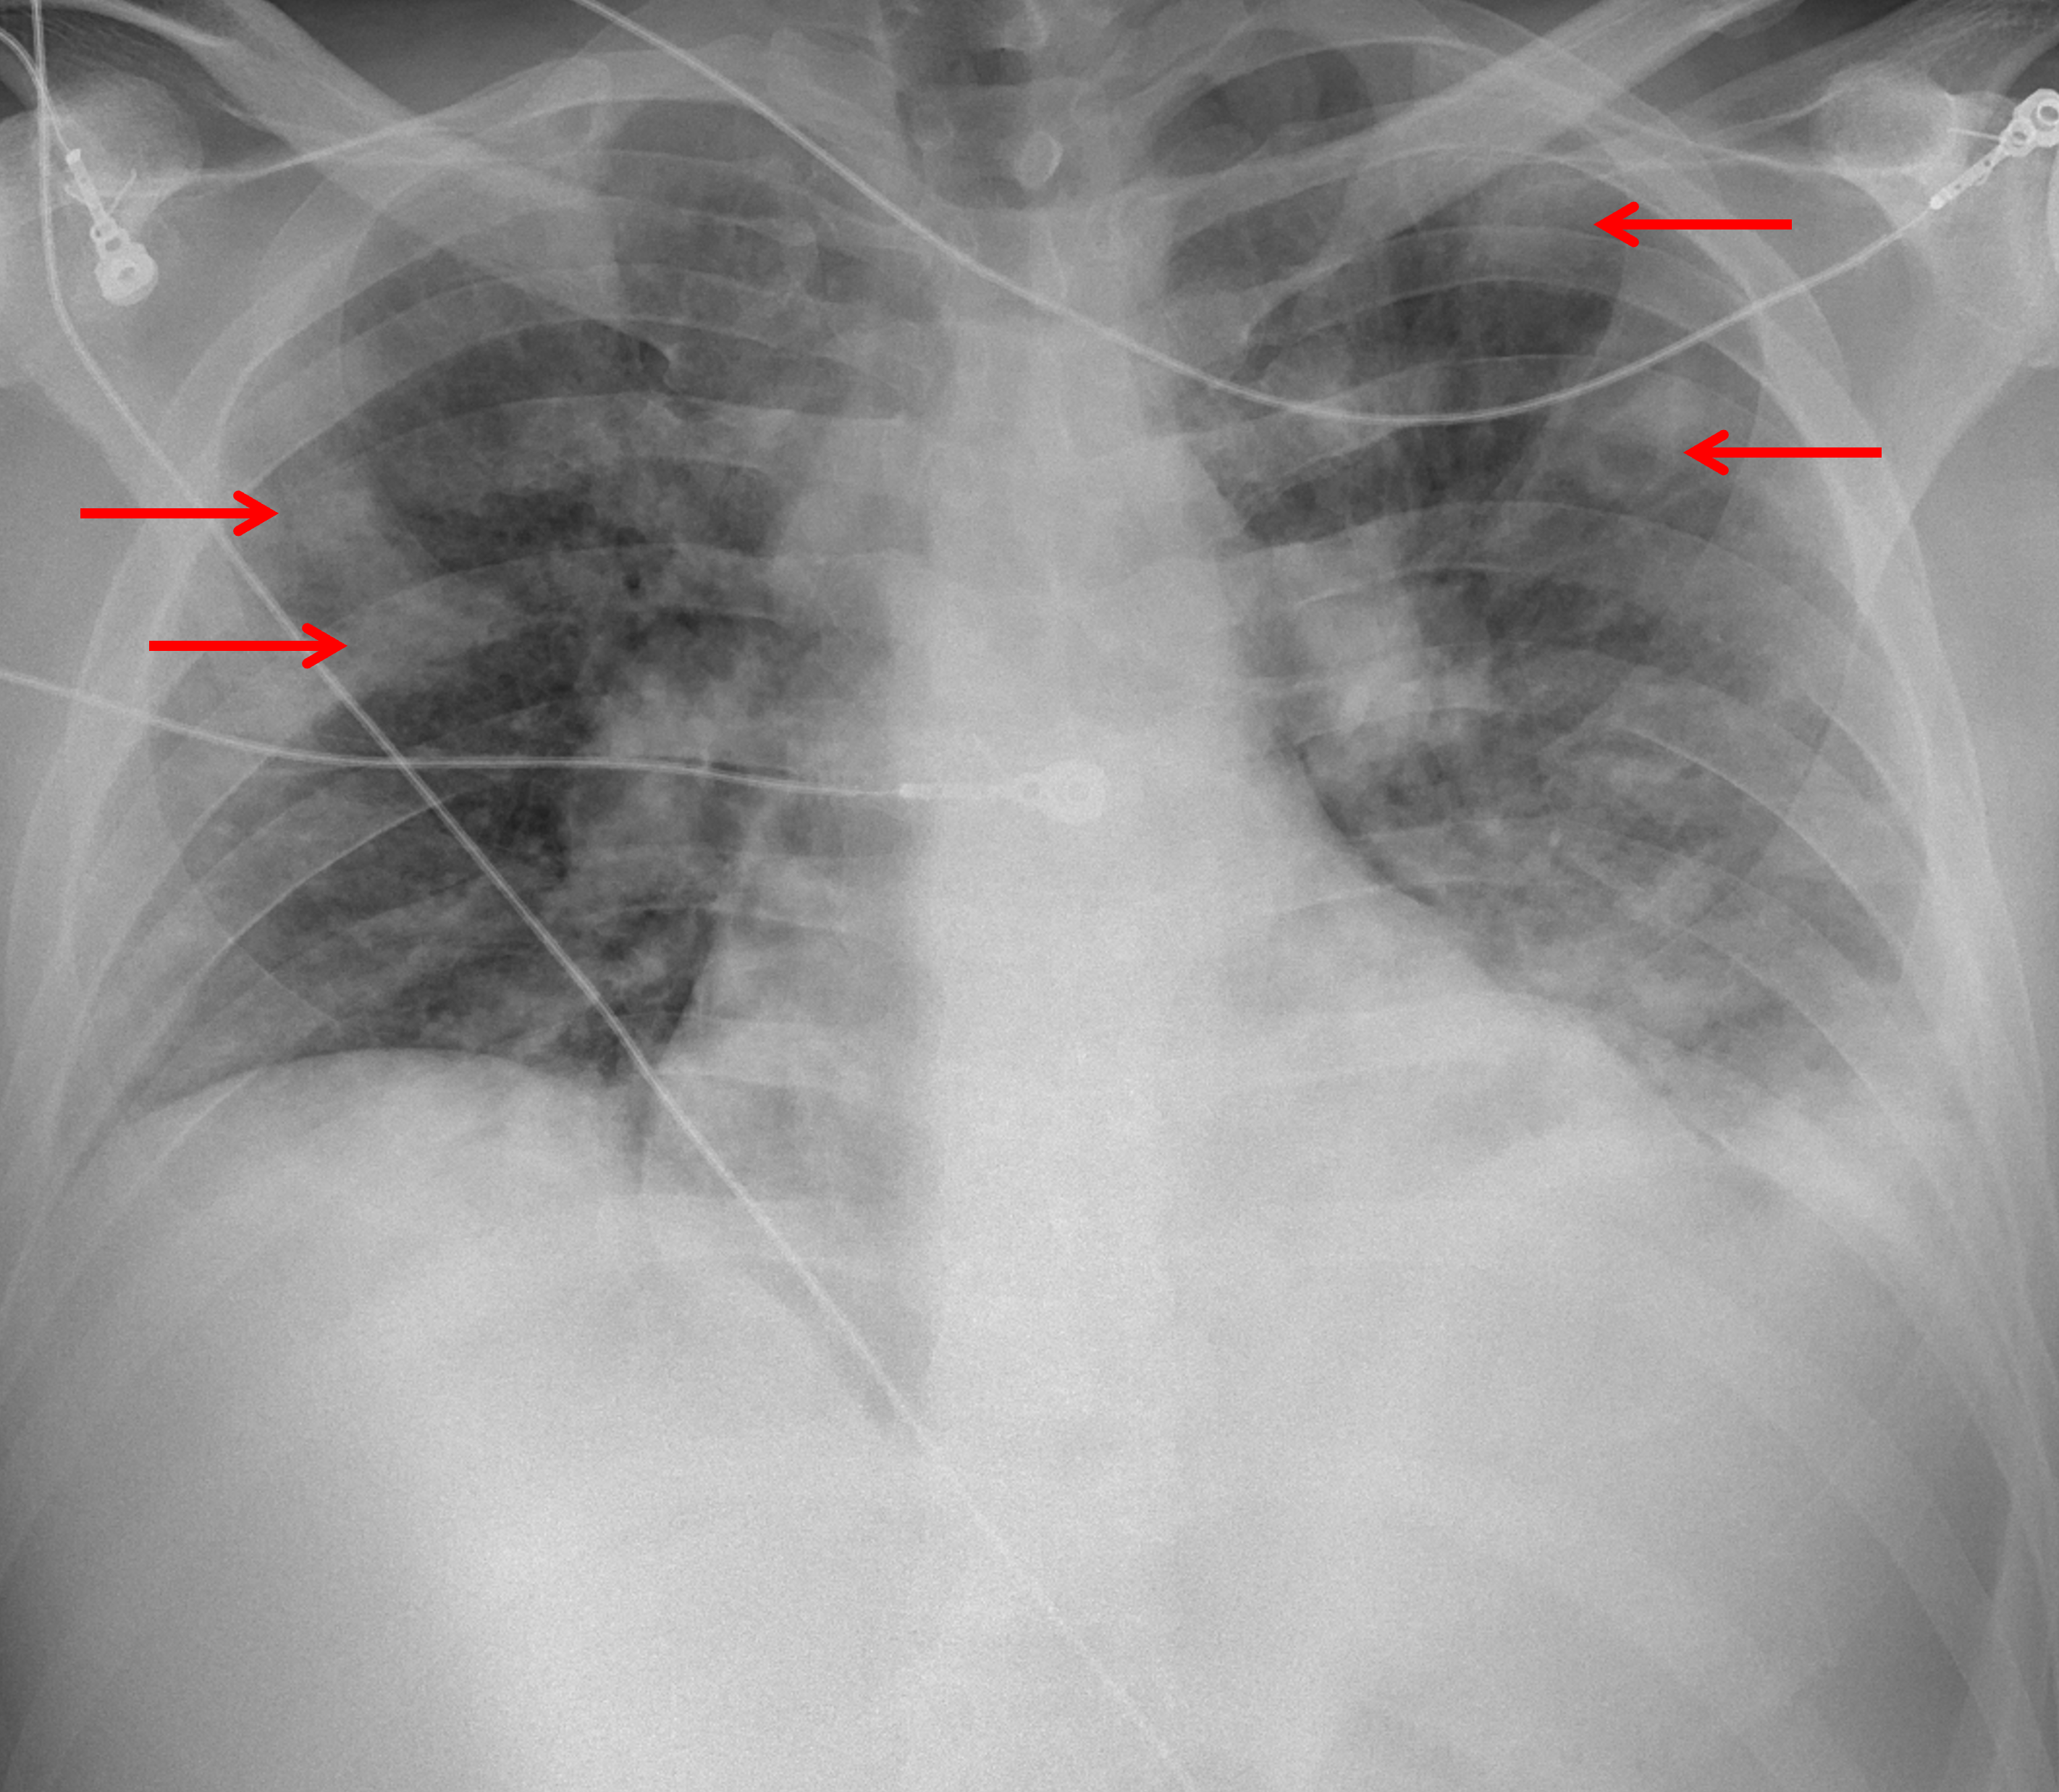

Age: 43

Sex: Male

Indication: Sepsis

Sample ReportMultiple bilateral pulmonary nodular opacities, several of which demonstrate central cavitation. In this patient with reported sepsis, the primary consideration is septic embolic disease. Consider chest CT and/or echocardiography for further evaluation. Recommend imaging followup to resolution to exclude underlying malignancy.

Small left pleural effusion with overlying atelectasis and/or airspace disease related to aspiration or pneumonia.